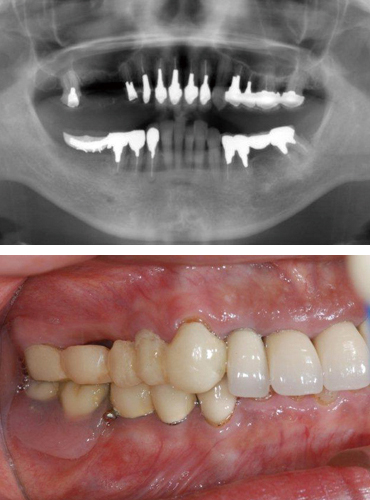

インプラント治療を行う前の検査として、一般的にはレントゲン撮影による術前診査が行われますが、レントゲン撮影によるレントゲン像は全顎的な診査を行うためにはとても有効ですが、インプラント治療の術前検査としては完璧なものではありません。

例えば、インプラント手術において危険領域となる神経管や血管の位置や骨幅、骨質などを正確に診査・診断するためにはCTによる精密検査は欠かすことはできません。

当院では、まず審査・診断を行い、CTによる精密検査、コンピューター3Dシミュレーションでのインプラント手術設計、サージカルガイドによるガイデッドサージェリーでのインプラント治療、治癒期間という流れになっております。